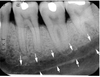

This is an air-containing cavity in maxilla, margins are made by a thin layer of dense bone

maxillary sinus

The anterior border of the maxillary sinus often intersects a line formed by what

floor of nasal fossa

maxillary sinus involving roots of maxillary premolars and molars

This cheek bone extends laterally from maxilla over the roots of maxillary posterior tooth

zygomatic arch

zygomatic bone